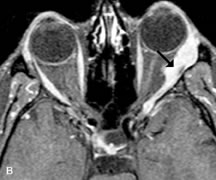

Breast carcinoma metastatic to the orbit has been demonstrated to be hypointense to the surrounding orbital fat on T1-weighted studies and hyperintense on T2-weighted images and has an affinity to the extraocular muscles (Fig. 20).50,64 The MRI characteristics of prostate carcinoma metastatic to the orbit have been described as involving the greater and lesser wing of the sphenoid, orbital roof, and optic canal. Diffuse bone hypertrophy with isointense or slightly hyperintense tissue on T1-weighted images represents the osteoblastic carcinomatous bone infiltration. Contrast enhancement is variable on T1-weighted and fat-suppressed images.65

Fig. 20. A. T1-weighted MR scan demonstrates nodular enlargement of both medial rectus muscles (arrows). B. T1-weighted fat-suppressed contrast-enhanced scan confirms the presence of small metnstatic deposits within the muscles (open arrows).